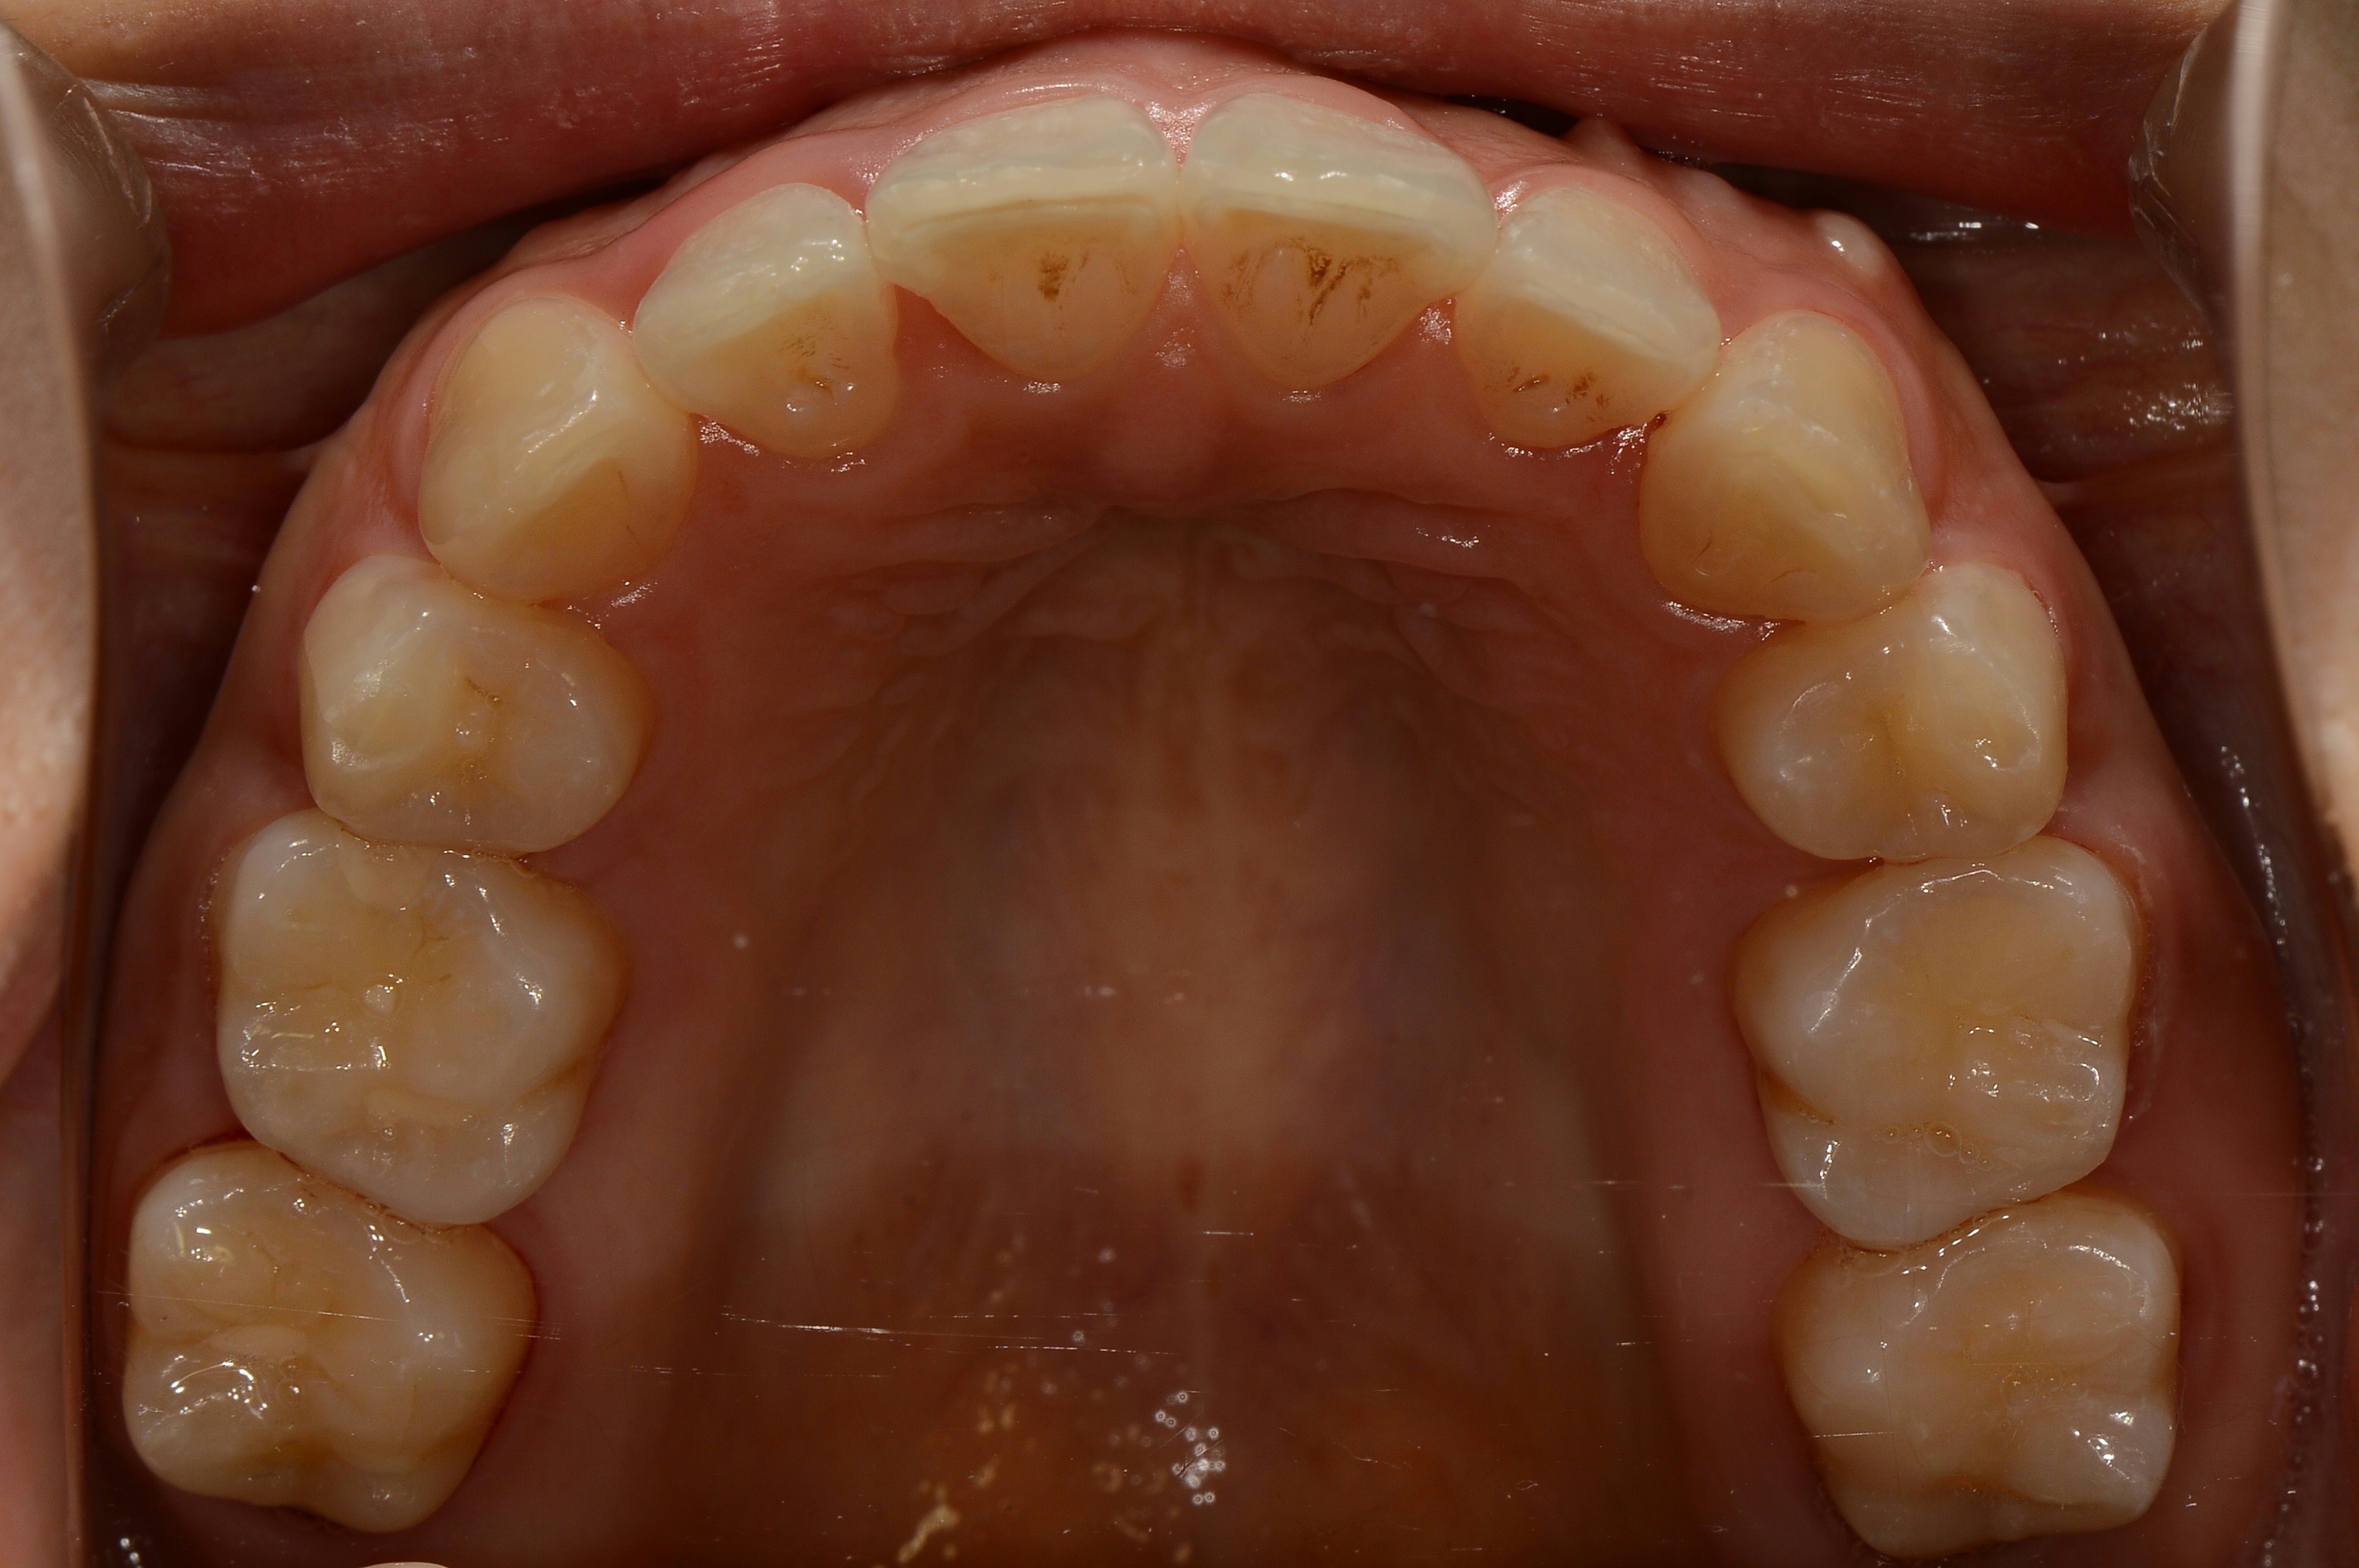

치료 전 사진입니다.